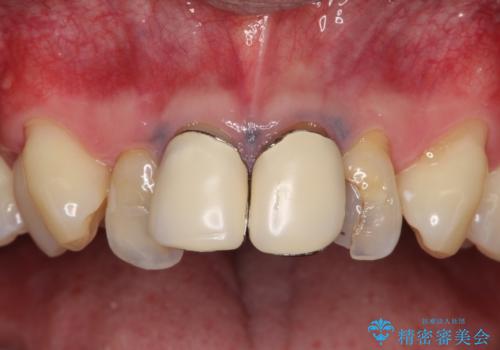

上の前歯の4本が神経の処置がされており、前から2番目の歯が内側に入り込んでしまっていました。

また、金属で治療された根本の歯茎が黒く変色(メタルタトゥー)しており、余計に見た目がよくない状態となっておりました。

矯正治療で前歯の歯並びを整えてからセラミックほ装着する計画としました。